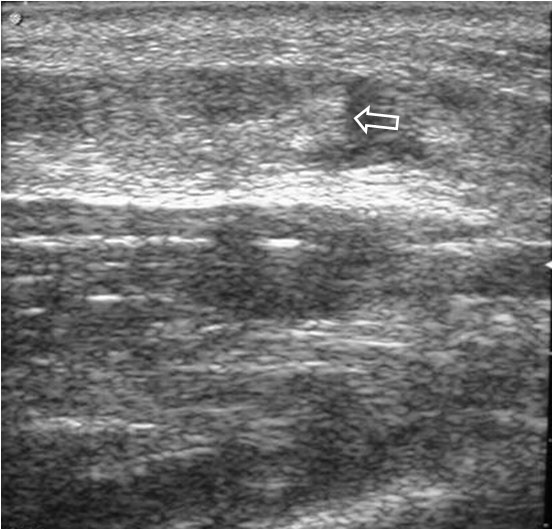

SIGNO DEL BADAJO Y SIGNO DEL HALO O DIANA

Ambos son signos ecográficos de rotura muscular. En el corte longitudinal al eje muscular, el «badajo» corresponde a la imagen redondeada del extremo retraído del músculo, rodeado de hematoma.

Signo ecográfico de rotura muscular en el corte transversal al eje del músculo. El signo corresponde al músculo retraído rodeado de un halo de hematoma.

El Signo del halo también se ve en la rotura muscular pero es un signo visible en el corte transversal al eje del músculo. El signo corresponde al músculo retraído rodeado de un halo de hematoma.